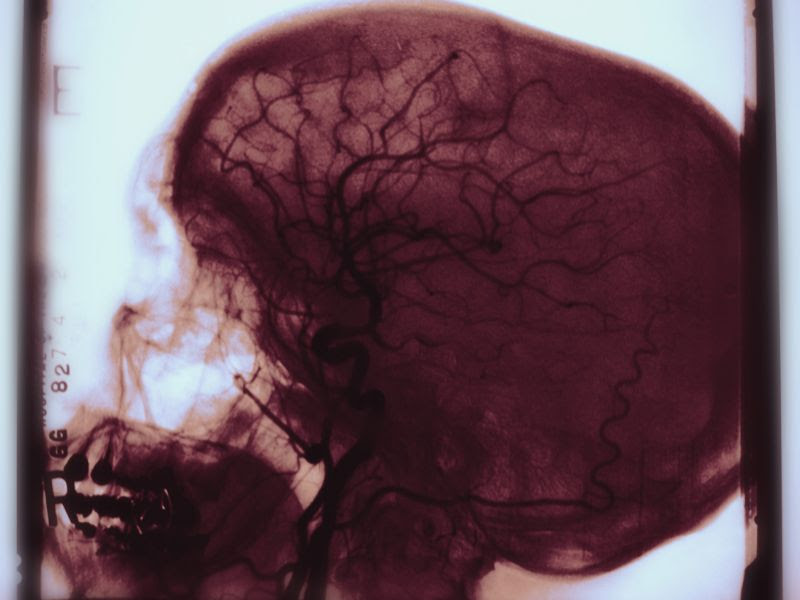

According to the American Stroke Association, only about 15 percent of strokes are caused by runaway bleeding in the brain; the other 85 percent are caused by a clot.

And while it makes sense to use the clot-busting tissue plasminogen activator (tPA) to break up a brain clot, it would seem counterproductive to use the same drug in the case of a bleeding stroke.

The doctors explained that tPA is used to clear the brain’s ventricles of blood that has pooled there as a result of the hemorrhagic stroke.